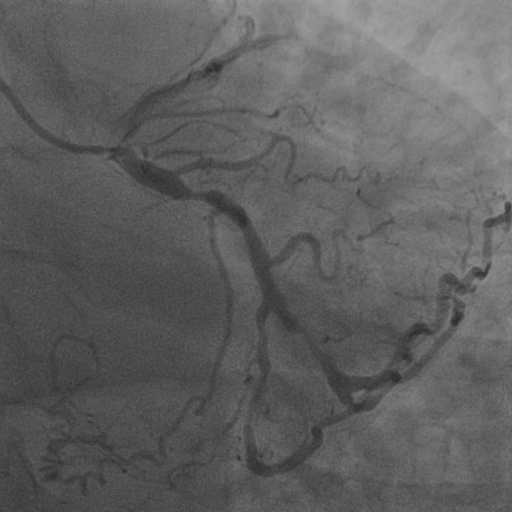

4.1 XACV Dataset

We collect 111 complete records of coronary artery X-ray videos, encompassing the injection, flow through the blood vessels around the heart, and dissipation of the contrast agent. Subsequently, we establish the XACV (X-ray Angiography Coronary Video) dataset. Each video consists of varying numbers of high-resolution coronary artery X-ray images. We invite experienced radiologists to annotate the vascular regions, focusing on one or two frames where the contrast agent is most prominent in each video. The XCAD dataset contains only a single image, and the CADICA video dataset does not provide corresponding ground truth. Therefore, in the following experiments, we conduct all the analyses on our collected XACV dataset and the corresponding GT for each sequence. In Figure 5, we show that compared to other publicly available datasets, XCAD [33] and CADICA [19], our dataset exhibits finer annotations in the vascular regions, providing an advantage for future related tasks. The development and use of our dataset have been approved by our institution’s IRB.